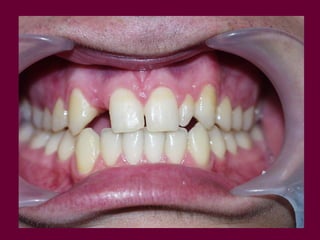

Feo